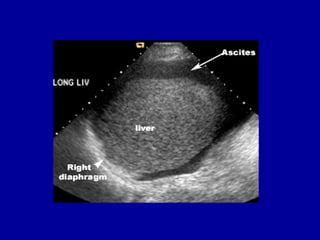

• USG

-site for paracentesis

-100ml fluid

-uncomplicated ascites

homogenous ,freely mobile, anechioc

collection in peritoneal cavity,deep

acoustic enhancement